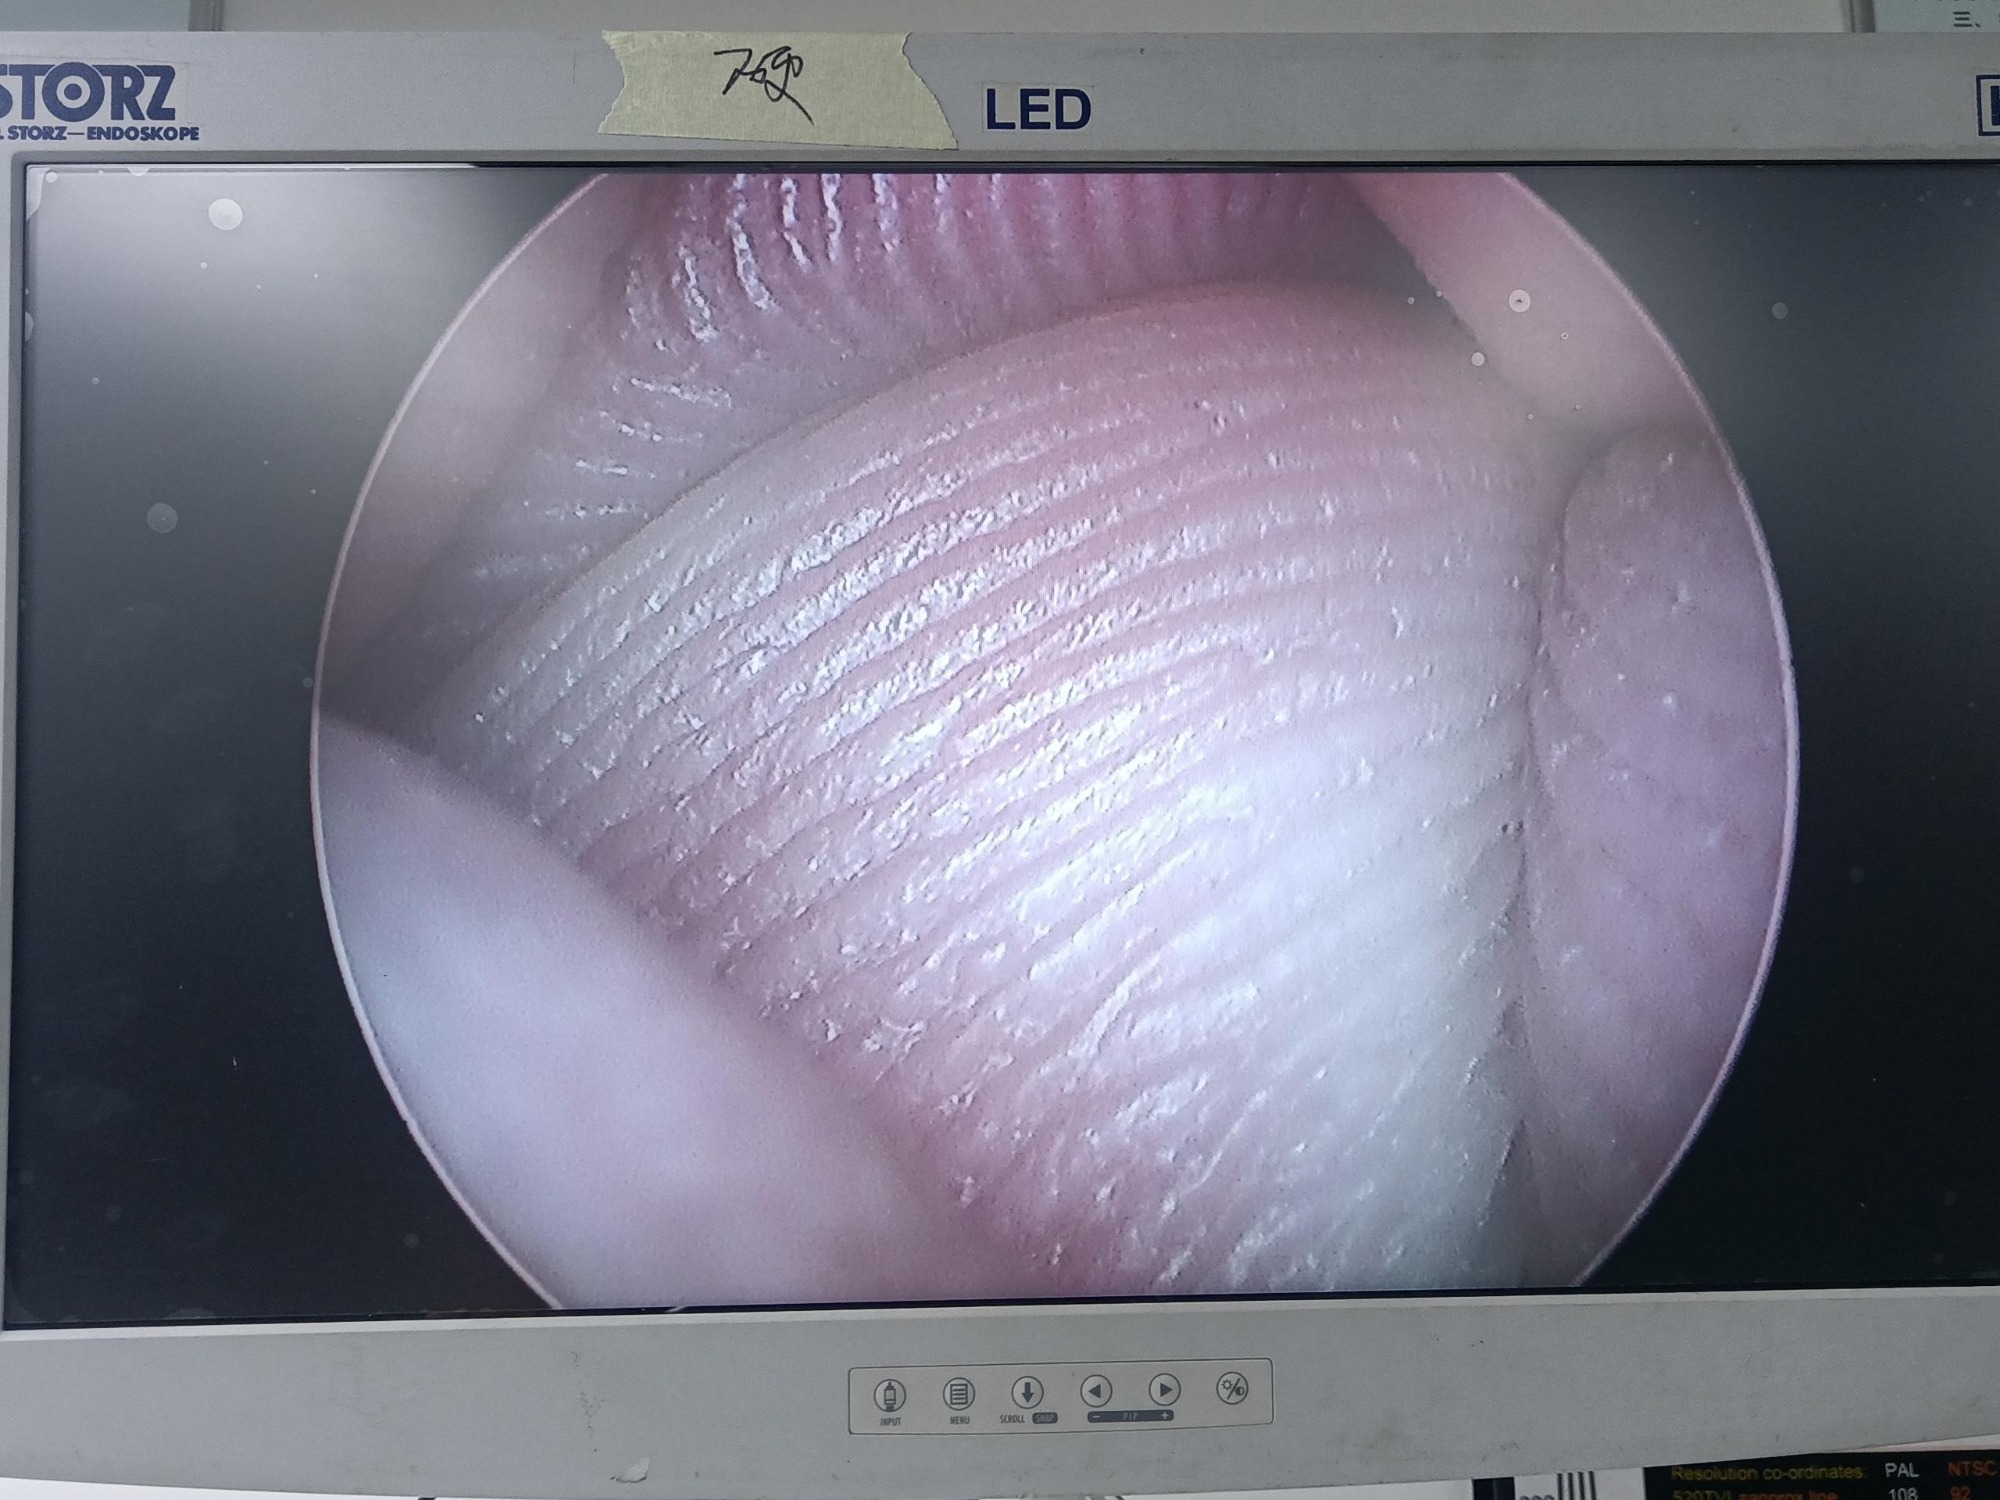

電切鏡的介紹及Wolf狼牌電切鏡8650.414維修案例分析

設備型號Wolf狼牌電切鏡8650.414

故障內容圖像模糊,棒透鏡破碎,導光錐破碎,目鏡罩破碎,鏡身有磕碰,但不影響使用。

維修方案更換棒透鏡、導光錐、目鏡罩,校對圖像,內窺鏡抗震蕩抗沖擊性能測試,內窺鏡密封性性能檢測;內窺鏡抗震蕩性能測試,內窺鏡冷熱沖擊性能檢測。